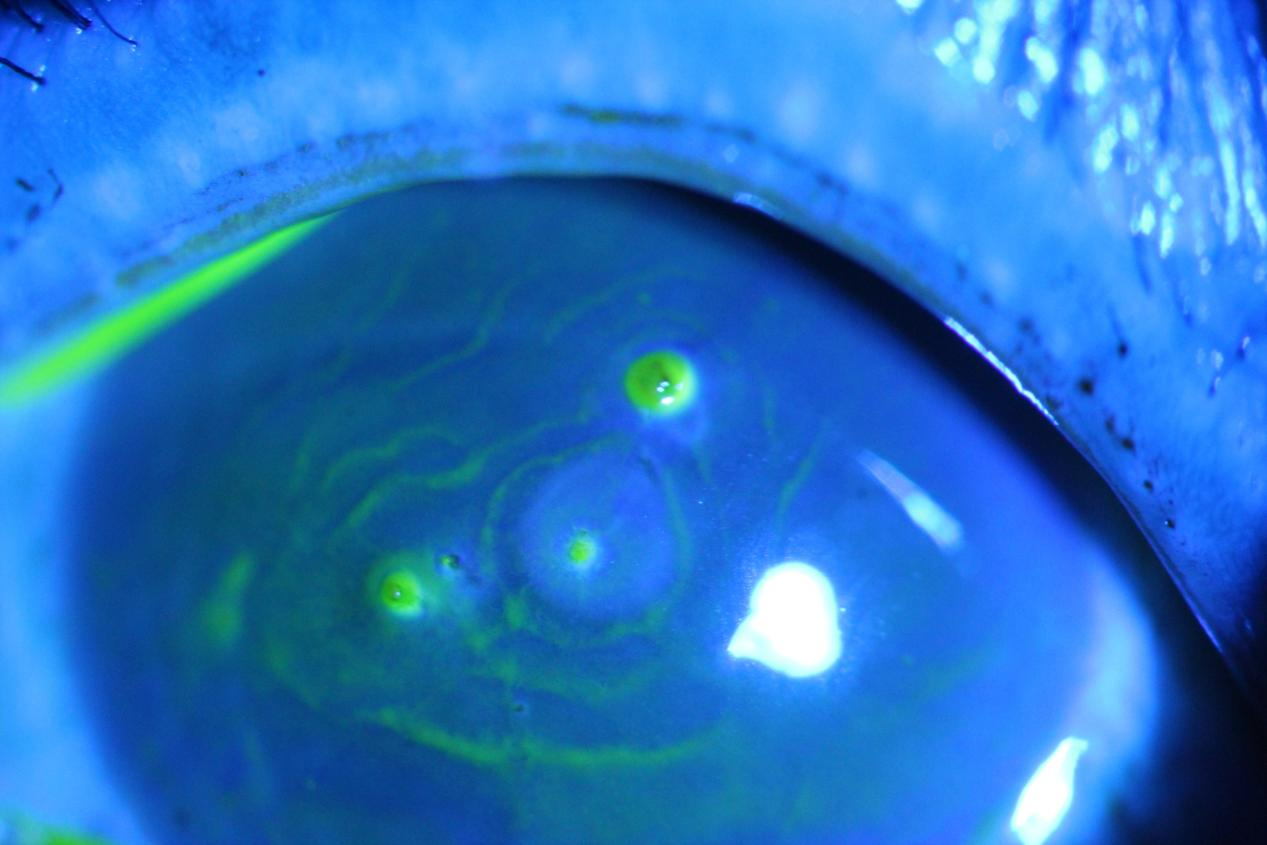

(右眼荧光素染色下眼前段照相如图所示)

急诊眼科医生赖琪珍接诊后,迅速为钟女士进行全面眼部检查。视力检查显示,其右眼裸眼视力仅为指数/10cm(即眼前10厘米处仅能分辨手指数量),左眼裸眼视力0.6;眼压检查提示右眼15mmHg、左眼17mmHg,处于正常范围。而专科检查的结果让医生倍感棘手:钟女士右眼球结膜充血明显,角膜中央有4根板栗刺扎入,更危险的是上方有一根约3-4mm长的板栗刺穿透角膜进入前房,前房水已出现混浊,瞳孔圆且居中,但对光反射迟钝,瞳孔缘 可见炎性渗出,晶状体也已出现混浊。